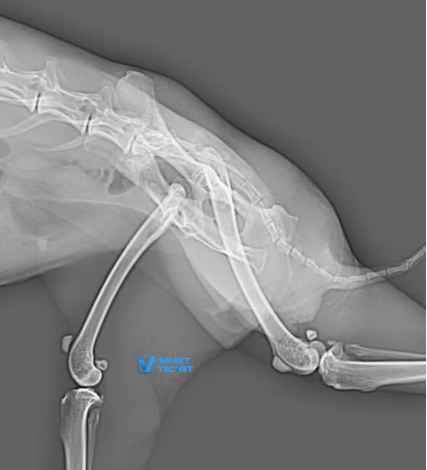

Lili, a two-year-old female rabbit, fell from her owner’s arms, resulting in lameness of the right leg. Radiographs of the pelvis and right hindlimb (excluding the area from mid-tibia to foot) were prepared and found to be of good quality. The radiographs revealed a complete luxation of the right coxofemoral joint, with a dorso-cranial displacement. Both acetabula and the left hip appeared normal. Hip dysplasia was not present. All other bones and joints of the hind limbs were normal, with no additional radiographic abnormalities identified. The final diagnosis, based on the radiographic findings, was traumatic dorso-cranial luxation of the right hip joint.